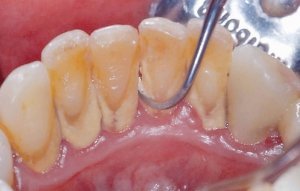

中度歯周病の患者様 ルートプレーニング

ルートプレーニングとは特殊な器具で歯周ポケットの奥にこびりついた歯石を除去する方法です。中度歯周病の場合、歯石がある程度深い位置に付着しているため、それを除去します。痛みや出血を伴う為、麻酔を使用して治療します。

中度の方への深層部洗浄

歯周ポケットの奥深くに歯石がある場合は、ルートプレーニングを実施します。表面麻酔や電動麻酔を使用し、痛みを感じさせない配慮をした上で、マイクロスコープで見守りながら原因菌を徹底的にリセットします。